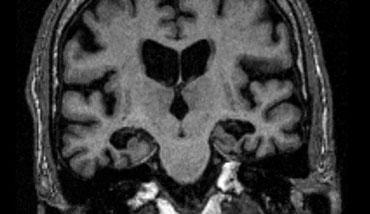

Hình ảnh mặt phẳng coronal cho thấy hồi hải mã, cấu trúc chính liên quan đến nhiều thể sa sút trí tuệ.

Điểm MTA cần được đánh giá trên chuỗi xung T1W mặt phẳng coronal tại một vị trí lát cắt nhất quán.

Chọn lát cắt qua thân hồi hải mã, ở mức cầu não trước.